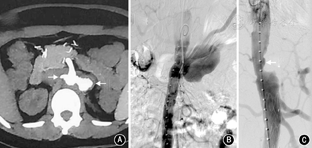

患者女,35岁,因发作性腰背疼痛1年,加重2个月余,于2014年12月入住北京协和医院。患者于2013年12月中旬无明显诱因出现头痛、心慌、大汗,无恶心、呕吐,未重视。2014年1月,患者因头痛伴血压明显升高至200/110 mmHg(1 mmHg=0.133 kPa)就诊于外院,左肾肾小球滤过率(GFR) 7.48 ml/min,超声提示左肾明显萎缩,大动脉造影显示左肾动脉起始段假性动脉瘤形成,压迫左肾动脉导致远端不显影;遂行左侧无功能肾切除术。术后病理提示左侧肾盂组织慢性炎,左肾组织间质少许慢性炎细胞浸润并玻璃样变性,左输尿管残端黏膜组织慢性炎。2014年4月,患者突发少尿,血肌酐(Cr) 795 μmol/L,考虑急性肾功能衰竭,开始行肾脏替代治疗,腹部增强CT提示L1水平腹主动脉左侧动脉瘤,大小约1.9 cm×1.7 cm,右肾动脉闭塞,右肾实质未见异常,腹膜后肿大淋巴结,腹主动脉周围可见软组织密度影包绕,增强扫描未见明显强化(图1A)。肾动脉造影提示右肾动脉主干仅线形显影,余完全闭塞。2014年5月尝试行右肾自体肾移植术,但术中发现肾动脉及其分支全部堵塞,遂切除右肾。术后病理显示右肾脏动脉间叶组织肿瘤,结合免疫组化染色符合血管内膜肉瘤,可见右肾脏肾小球及肾小管透明变性、凝固性坏死伴灶状炎细胞浸润及间质纤维结缔组织增生,右输尿管残端及右肾周脂肪组织未见肿瘤组织(图2);免疫组化:波形蛋白(Vimentin)(+),肌动蛋白(actin)(+),增殖指数(Ki-67)(+,约10%),簇分化抗原(CD)31、CD163、CD68、CD3、白细胞共同抗原(LCA)、B细胞淋巴瘤白血病基因-2(BcL-2)、CD34、高分子量钙调结合蛋白(h-Caldesmon)、平滑肌肌动蛋白(SM-actin)、CD21、CD35、D2-40、CD123、CD20、S-100、第Ⅷ因子相关抗原(FⅧ-RAg)、结蛋白(Desmin)、间变性淋巴瘤激酶(ALK)、CD99、角蛋白(CK)、上皮膜抗原(EMA)、CK18、黑色素瘤相关抗原(HMB45)均(-);未进行后续辅助治疗。2014年7月,患者复查胸腹部CT血管造影(CTA),提示腹膜后肿物包绕T12、L1椎体水平腹主动脉、腹腔干及双肾动脉残端,左肾动脉残端瘤样扩张,大小约2.3 cm×2.1 cm×2.3 cm;患者未治疗。2014年12月3日,患者因腰部剧烈疼痛复查肾动脉超声提示腹主动脉瘤可能性大,大小约5.7 cm×4.0 cm,左肾动脉主干受压前移。当日夜间,患者血压最高达190/110 mmHg,次日早晨患者因失血性休克急诊行大动脉造影提示左肾动脉残端假性动脉瘤(图1B),考虑左肾残端动脉瘤破裂出血,遂行腹主动脉假性动脉瘤腔内隔绝术,术中对支架行肠系膜上动脉开窗。2015年1月,患者上厕所时突发右侧腰背部持续钝痛;腹主动脉CTA考虑腹主动脉假性动脉瘤形成。主动脉造影提示原主动脉支架上方造影剂轮廓不规则,考虑主动脉假性动脉瘤形成(图1C),遂再次行腔内隔绝术,支架放置于腹腔干上方。术后行PET/CT提示腹主动脉(T10~L2水平)周围巨大肿块,包裹腹腔干及肠系膜上动脉,范围约11.8 cm×9.0 cm×10.0 cm,考虑恶性病变,全身其余部位未见明确转移(图3)。出院后患者未行辅助治疗。2015年3月,患者因心力衰竭去世。